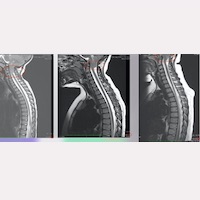

従来の基準と終糸システム®による外科的治療のリスクとメリットの関係性に基づく、アーノルド・キアリ症候群、脊髄空洞症、特発性側弯症およびその他の関連疾患への外科的治療適用の違い もっと見る » 2024/09/20